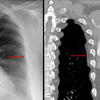

Aortic nipple

Ex 1 CT

Date: 03/23/2004

Views: 5389